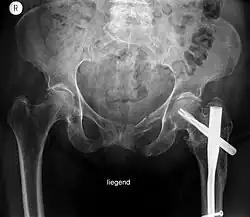

Behandelter Beckenbruch

Stabile Beckenfrakturen werden konservativ behandelt. Unter krankengymnastischer Begleitung ist frühestmögliche Mobilisation anzustreben.

Instabile Beckenfrakturen müssen meist notfallmäßig durch eine Beckenzwinge oder einen externen Fixateur stabilisiert werden, um eine innere Blutung durch die Kompression zu stoppen. Blutungen verbieten eine Eröffnung des Beckens. Später werden die Brüche operativ durch Platten oder Schrauben fixiert. Mobilisation ist nach etwa zwei Monaten möglich.